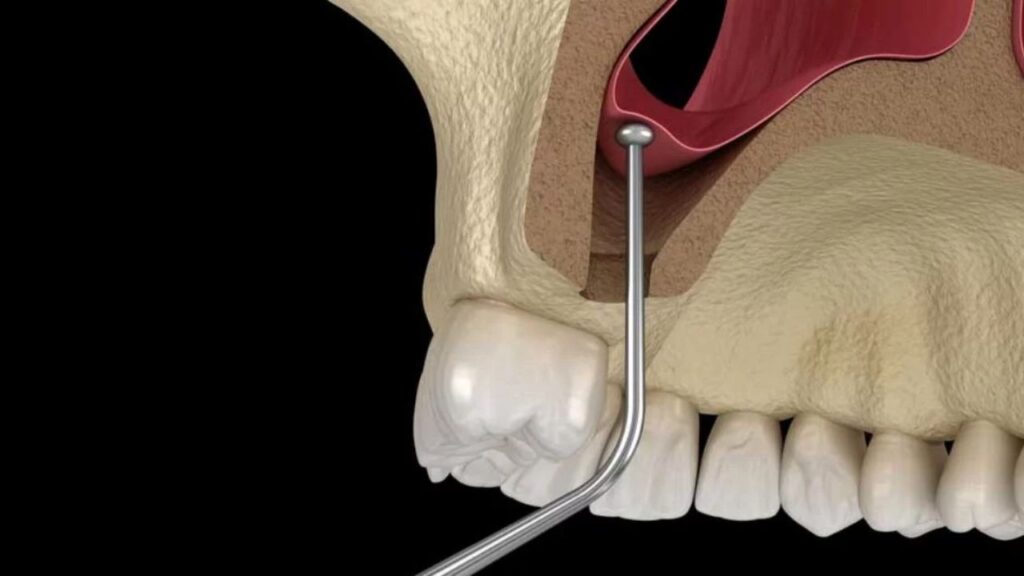

Elevación del seno maxilar

La elevación del seno maxilar es un procedimiento quirúrgico necesario cuando el hueso del maxilar superior no tiene suficiente altura para colocar implantes dentales. Este problema ocurre principalmente en la región posterior del maxilar, donde se encuentran los senos maxilares, cavidades naturales que pueden ocupar el espacio óseo requerido para el implante.

Durante esta cirugía, se eleva la membrana del seno maxilar y se inserta un injerto óseo para aumentar la altura del hueso. Esto facilita la colocación del implante. Es un procedimiento clave para pacientes con pérdida ósea en esta zona.